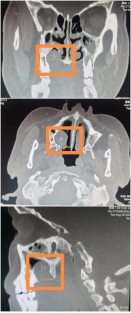

为进一步提升医护人员对CT增强扫描中过敏反应的应急处置能力,保障患者就医安全。近日,由西安市红会医院医务部、控制院内感染办公室、医学影像中心CT室共同组织,联合多个相关科室开展了一场过敏反应应急演练活动。演练模拟了一位患者在CT增强扫描过程中突发造影剂过敏反应的…